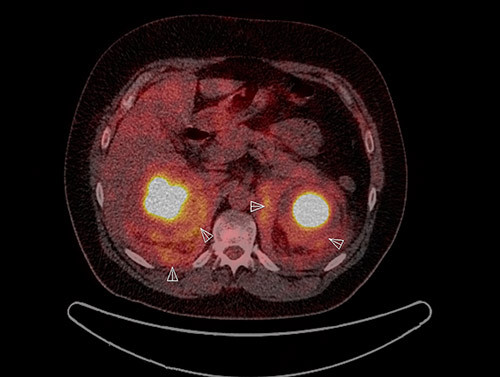

18FDG PET-CT viste økt opptak perirenalt, oppfyllinger i begge orbitae, periaortalt, i myokard og i oppfylling rundt hjertet samt i beinmargen i distale deler av begge femora og proksimale tibiae (fig 3, fig 4). I nyrene var det dilatasjon av calyces, men ikke dilatasjon av det ekstrarenale nyrebekken eller uretre. Ultralyddoppler av nyrearterier viste ikke tegn på nyrearteriestenose. I lungene var det lette mattglassfortetninger og sparsom bilateral pleuraeffusjon. Spirometri viste lett redusert belgfunksjon av restriktiv type. Ekkokardiografi viste grensestor venstre ventrikkel med god venstre og høyre ventrikkelfunksjon, i tillegg til lett perikardvæskebrem på 0,5 – 0,6 cm uten hemodynamisk betydning.